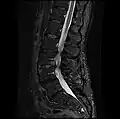

MRI lumbar spine post-hemilaminectomy (sagittal T2 FRFSE)

-

MRI lumbar spine post-hemilaminectomy (sagittal T1 FSE)

Contrast MRI lumbar spine post-hemilaminectomy (sagittal T1 FSE FS)